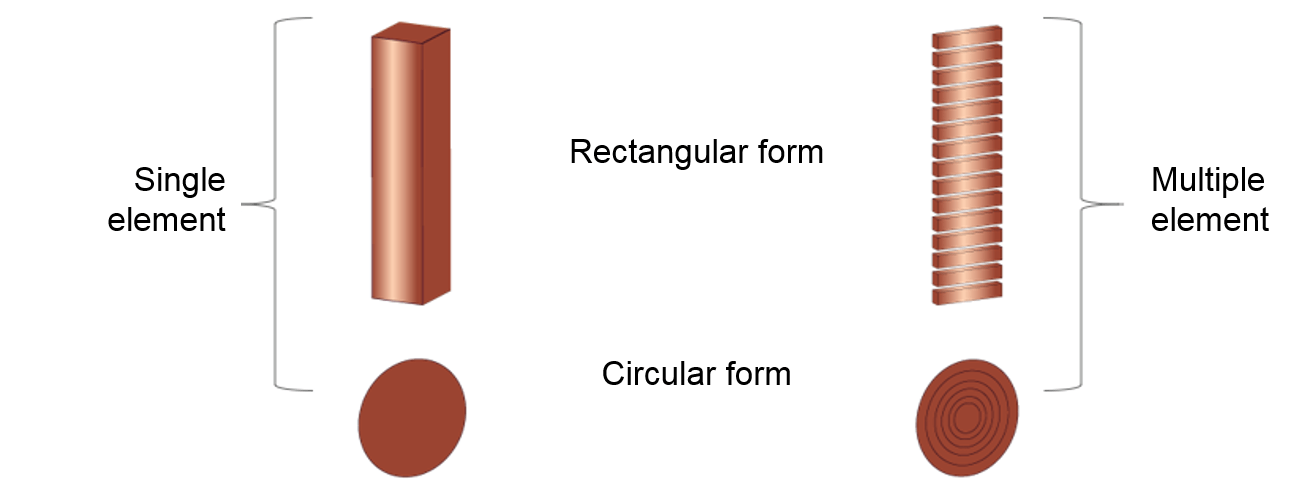

As we mentioned previously, the ultrasound transducer is composed of one or more crystals called piezoelectric crystals. It might be composed of a single element or a band of multiple elements in rectangular or circular form. Besides, the element thickness is determined based on what resonance frequency is desired. Multi-element ultrasound transducers have the advantage that the ultrasound beam can be steered and focused electronically without moving the transducer by using electronic/digital delays in the activation of the different piezoelectric elements.